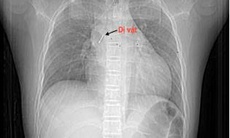

Dị vật là sợi dây chun được bác sĩ lấy ra thành công.